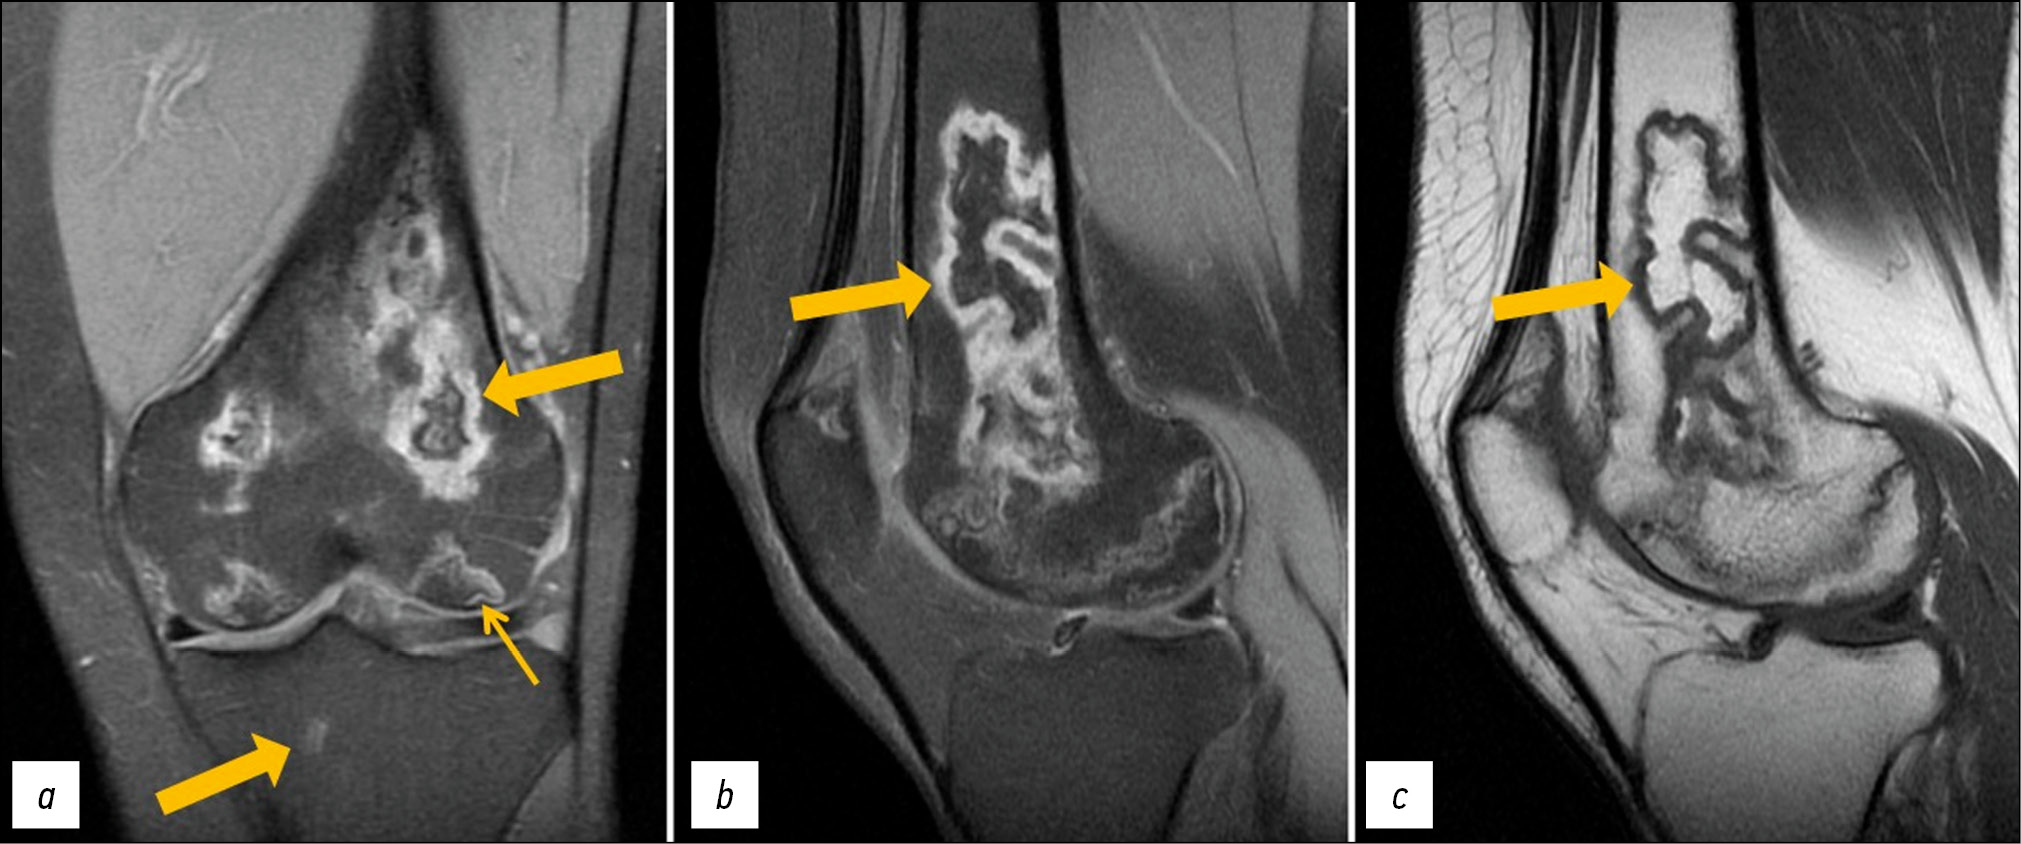

MRI of the left knee joint: lesions in the distal parts of the femoral diaphysis and femoral condyles (with involvement of the articular surface) as well as in the patella, inhomogeneously hyperintense on PD-weighted (proton-weighted) images with fat suppression and hypo-/isointense on T1-weighted images (T1WI), with an irregular (“geographic”) shape and yellow marrow signal areas visualized in the central parts (Fig. 1). MRI of the right knee joint: similar lesions of the bone marrow of both femoral condyles, with involvement of the distal metaepiphysis and articular surface of the lateral condyle as well as the patella. A perilesional “double line” sign is visualized over a short distance for some lesions (Fig. 2).

Fig. 2. Primary MRI of the right knee joint: PDWI with fat suppression in the coronal (а) and sagittal (b) plane and T1WI in the sagittal plane (с). Thick arrows indicate areas of bone marrow edema in the form of a heterogeneous, irregularly shaped (“geographic”) MRI signal of femoral condyles and patella; thin arrows indicate the “double line” sign in the form of internal hyperintense (granulation tissue) and external hypointense (osteosclerosis) lines on PDWI.